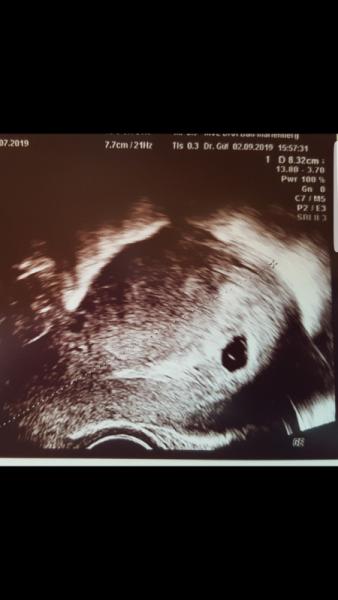

Schicke mal das Bild...

Bild zu

Hier das Bild im Anhang...

Wie gesagt, sein kann alles Das Bild habe ich zu Beginn der neuen ss nun vergraben...Man sah einen kugelrunden dottwrsack und ein winziges etwas direkt daran, was meine FA damals ganz optimistisch als Embryo gemessen hat mit 2 oder 3 mm ohne Herzschlag Meine Fruchthöhle war größer als deine. Ich drücke dir ganz fest die Daumen. Da du dir einen ziemlichen Kopf zu machen scheinst, würde ich dort früher als ende des Monats wieder auf der Matte stehen. Eine Woche nachdem man den Dottersack sieht, sollte man auf jeden Fall auch einen Embryo sehen.

Hey erstmal Glückwunsch. Mach dich nicht verrückt. Ich war rechnerisch das erste Mal bei 6+4 beim Arzt. Man konnte nichts sehen, ausser die fruchthöhle. Meine Ärztin sagte direkt, entweder die Schwangerschaft ist jünger oder es entwickelt sich wieder nichts. Zwei Tage später sollte ich wieder hin. Ich war total überrascht, denn innerhalb von zwei Tagen wurde aus nichts ein 3 mm großer Krümel mit Herzschlag. Bei dir auf dem Foto ist doch schon ein Dottersack zu erkennen. Da wird sicher such ein Zwerg sitzen.